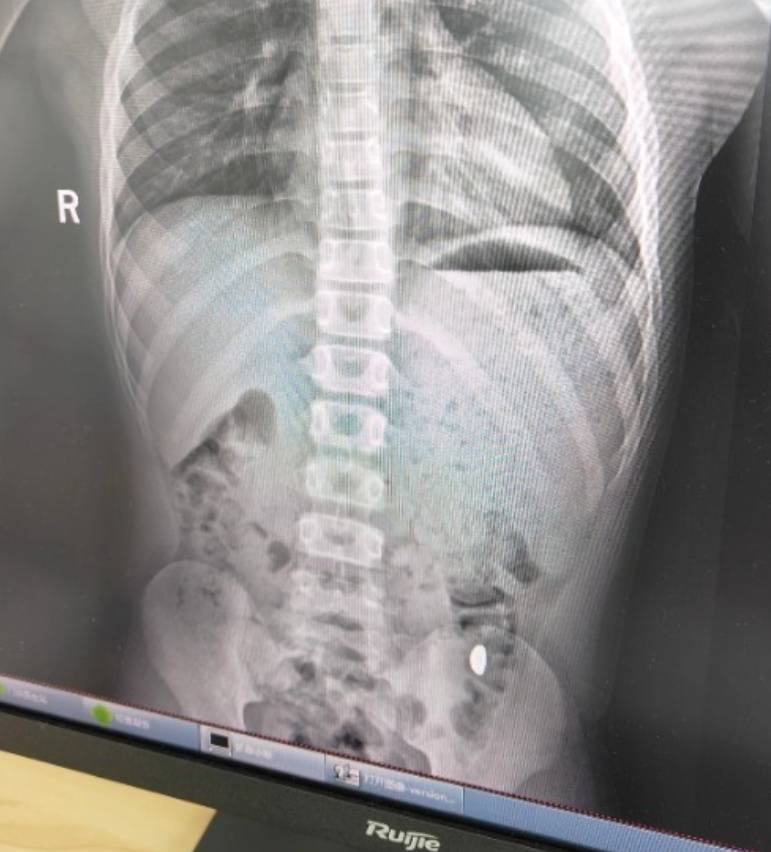

右下加亮点为金豆云币海外。